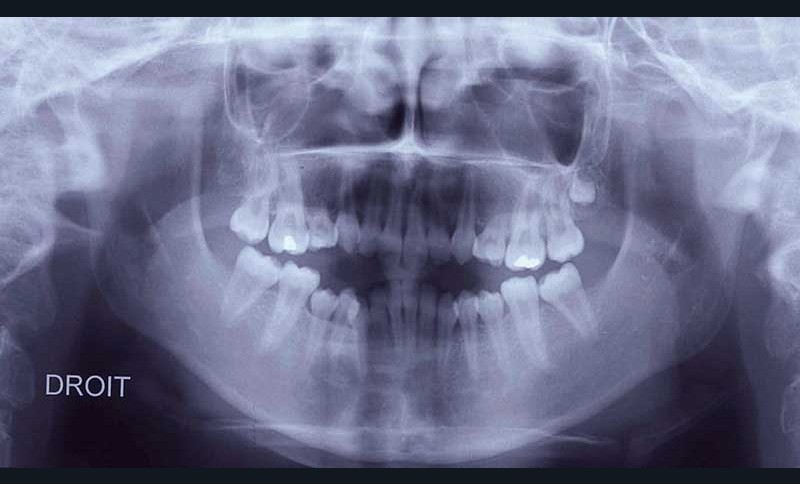

Pour les raisons précitées, les traitements orthodontiques menés en collaboration avec un chirurgien maxillo-facial sont de plus en plus fréquents [7]. Dans le cas clinique qui illustre cet article, il s’agit d’une jeune fille âgée de 13 ans lors la première consultation (fig. 1, 2, 3).

Sur le plan squelettique, elle présente une classe 3 par rétromaxillie dans un profil cisfrontal associé à une hyperdivergence faciale. La proalvéolie incisive maxillaire et la forte rétroalvéolie incisive mandibulaire singularisent le secteur alvéolo-dentaire (fig. 4 et 5).